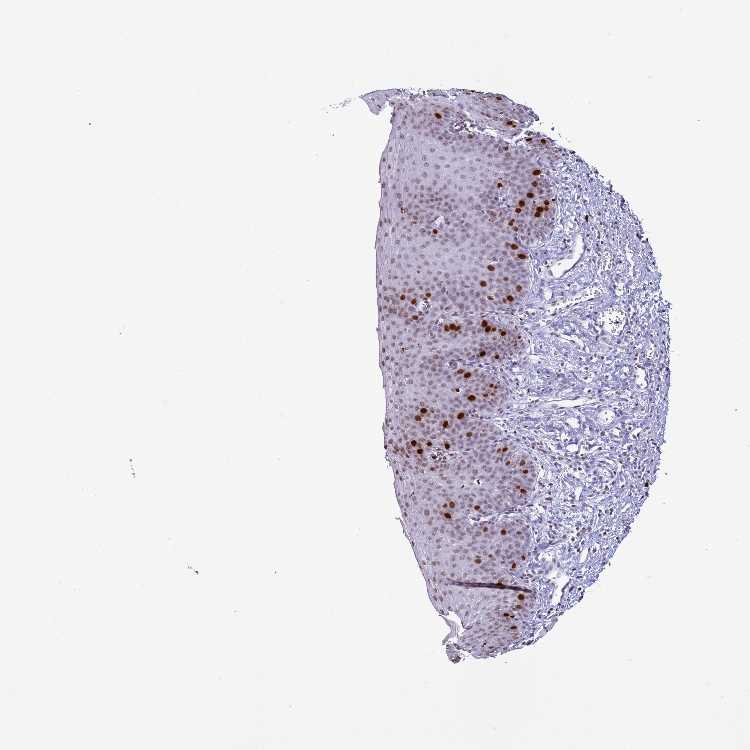

ESOPHAGUS - Antibody stainingi

Antibody staining in the annotated cell types in the current human tissue is reported as not detected, low, medium, or high, based on conventional immunohistochemistry profiling in selected tissues. This score is based on the combination of the staining intensity and fraction of stained cells.

Each image is clickable and will lead to virtual microscopy that enables deeper exploration of all samples and also displays staining intensity scores, fraction scores and subcellular localization as well as patient and tissue information for each sample.

Antibody HPA042201

Squamous epithelial cells Medium